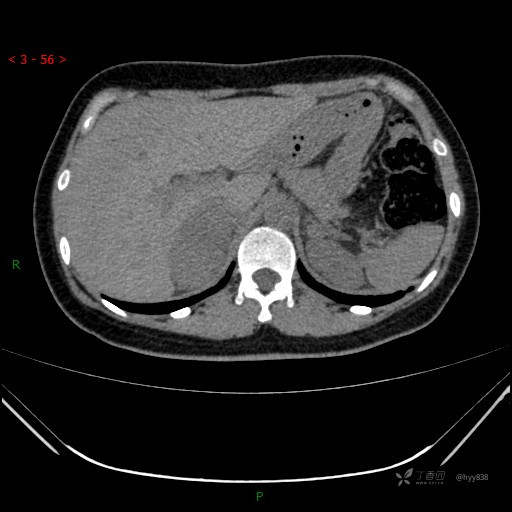

辅助检查:CT

动脉期